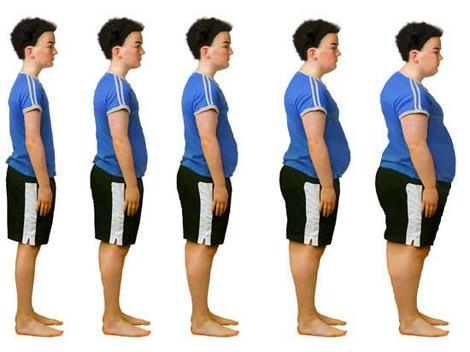

L‘obesità infantile è un rischio concreto in Italia dove moltissimi non fanno sport e non seguono un’alimentazione adeguata. A lanciare l’allarme è è il presidente della Società italiana di pediatria, Alberto Villani, presentando la Consensus su diagnosi, trattamento e prevenzione dell’obesità del bambino e dell’adolescente realizzata dalla Sip e dalla Società italiana di endocrinologia e diabetologia pediatrica.